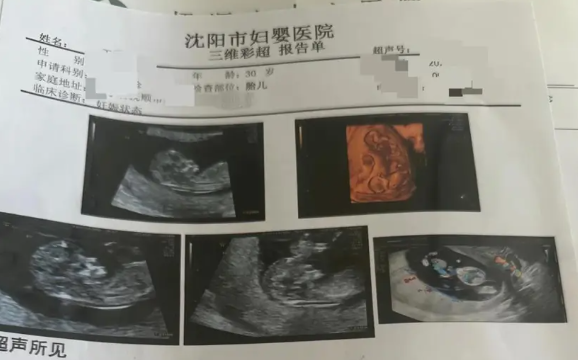

Một phụ nữ từ mang một thai đã đột ngột mang thai bốn thai chỉ trong vòng hai tháng

Một phụ nữ mang thai ở Trung Quốc đã trải qua tình huống cực kỳ hiếm gặp: từ chỗ được chẩn đoán mang thai một, sau đó lần lượt phát hiện thêm thai nhi qua từng lần khám, cuối cùng xác nhận mang...